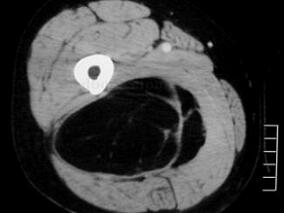

1小时条评论男57岁,起初仅面部水肿,其他未显示异常未予特殊处理,之后面部水肿有加重趋势,病情不断加重,最后竟诊断为纵隔肿瘤,伴附近淋巴结转移,已无法手术治疗。其疾病是怎样一步步恶化的呢?为何自初诊至明确诊断经历了3~4个月的时间? 一位男性病人,57岁。因一个半...